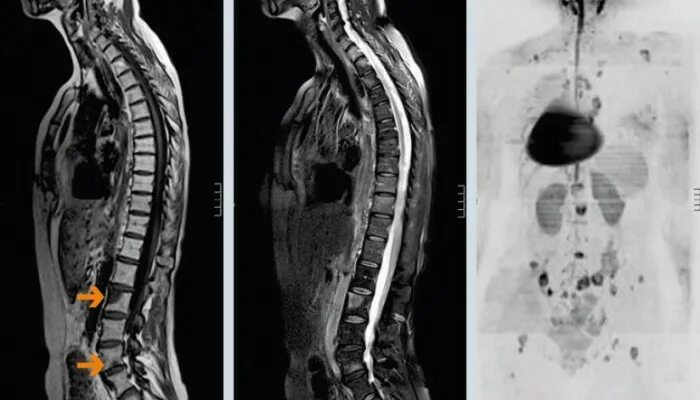

Сколько живут с метастазами в позвоночнике